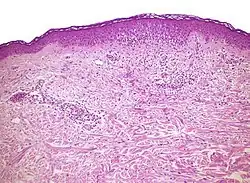

Micrograph of a vacuolar interface dermatitis with dermal mucin, as may be seen in lupus. H&E stain.

Lupus erythematosis Typical findings in systemic lupus erythematosus:[4]

• Fibrinoid necrosis at the dermoepidermal junction

• Liquefactive degeneration and atrophy of the epidermis

• Mucin deposition in the reticular dermis

• Edema, small hemorrhages

• Mild and mainly lymphocytic infiltrate in the upper dermis

• Fibrinoid material in the dermis around capillary blood vessels, on collagen and in the interstitium

• In non-bullous cases, perivascular and interstitial neutrophils are sometimes present in the upper dermis, with damage to blood vessels